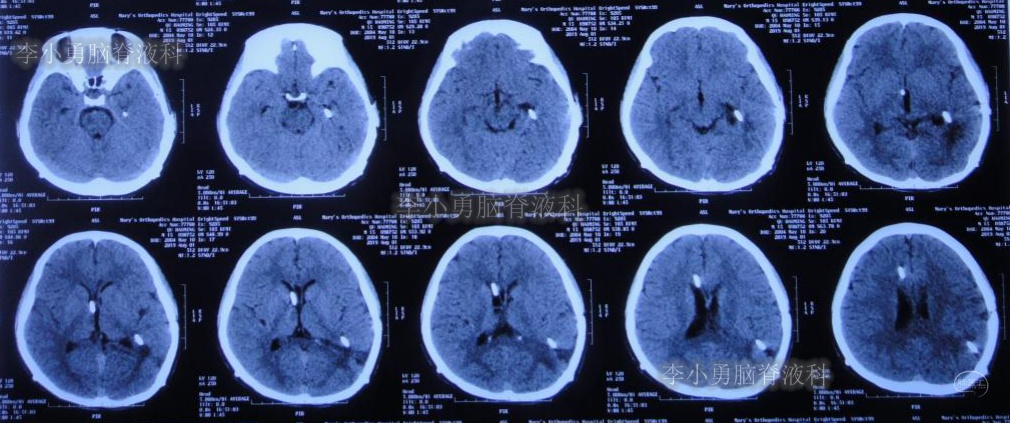

闭管40天后即2019年9月9日复查头颅CT(图-23):脑室仍无扩大。给予拔除右侧脑室外引流管并行左侧颞角-腹腔分流术。

图-23:2019年9月9日头颅CT:拔除右侧脑室外引流管后复查

出院后2个月即2019年12月9日,复查头颅CT示脑室系统较出院时无明显变化(图-25);但患者记忆力仍差。

图-25:2019年12月9日头颅CT

出院后9个月即2020年7月6日,再次复查头颅CT(图-26):未见异常。家属叙述:肢体活动正常,记忆力较前有些改善但较同龄人仍差,已重返校园(图-27)。

图-26:2020年7月6日头颅CT:未见异常